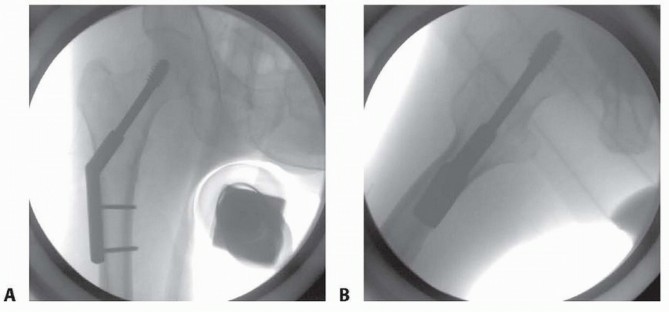

Minimally Invasive Fixation with a Sliding Hip Screw ### Positioning, Reduction, and Guidewire Placement The patient is positioned on the fracture table as noted earlier and in Chapter 40, except that we do not use a well-leg holder because of risk of compartment syndrome. Occasionally, in patients with adduction contracture, the well leg cannot be abducted enough with the hip extended to allow access of the C-arm. In these cases, the well-leg holder is used as described in Chapter 50. Fluoroscopic visualization is performed, and reduction is confirmed to be acceptable in all planes. 384 In femoral neck fractures, as opposed to intertrochanteric or pertrochanteric fractures, the reduction must be verified as anatomic if one is to expect stability and healing. In this approach, as opposed to the technique described in Chapter 50, the guidewire is inserted percutaneously by poking through the skin under the guidance of fluoroscopy and with use of an appropriate angle guide ( TECH FIG 7A). The guidewire is positioned at the center of the femoral neck and head as described in Chapter 50 ( TECH FIG 7B). If the fracture is rotationally unstable (transcervical, comminuted, widely displaced before reduction), an antirotational wire or screw should be placed up the neck across the fracture to prevent loss of reduction (see TECH FIG 6A). ### Incision and Preparation of Bone An incision is made beginning at the guidewire and extending distally for 4 to 5 cm ( TECH FIG 8A). A full-thickness skin-to-bone incision is made. Soft tissues are gently spread with a clamp, and an elevator is used to clear tissue from the lateral cortex distal to the pin entry site for the length of a two-hole plate. The guidewire is measured. The reamer is then set to this depth ( TECH FIG 8B). Fluoroscopy should be checked intermittently during reaming because the guidewire can migrate into the pelvis if bound by the reamer.

---

### TECH FIG 7 • A. Percutaneous insertion of a guidewire with angle guide. The guide is held alongside the leg and fluoroscopic views are obtained to verify parallel alignment. B. Fluoroscopic AP image showing insertion of guidewire, which has been stabbed through the skin.

Implant Placement The lag screw is then placed over the guidewire in standard fashion ( TECH FIG 9). The femoral neck-shaft angle has been set by placement of the guide pin, but it can be measured intraoperatively with a guide to select the appropriate implant. This is usually a 135-degree side plate if placed correctly. The side plate is then placed over the lag screw and gently worked through the soft tissues until it is placed into contact with the lateral cortex. The skin is quite mobile and elastic, and with a little stretching, the plate can be positioned easily. Final seating can be done with light blows of a mallet with the aid of a “candlestick” impaction device. A two-hole plate is sufficient. If lag screw was not placed with the key parallel to the femoral shaft, most systems allow this to be corrected by simply reapplying the T-handle screwdriver to the lag screw and turning the plate and screw as one unit until the plate fits appropriately. Usually, only two bicortical screws are needed through the side plate into the shaft. As mentioned earlier, appropriate films should be taken with the patient aslee This may include plain films if fluoroscopy is not adequate.

### TECH FIG 8 • A. After satisfactory position of the guidewire is verified on AP and lateral fluoroscopy, the incision is marked on the skin 4 to 5 cm inferior to the guidewire. B. The cannulated reamer is used to prepare the bone for the lag screw. 385 ### TECH FIG 9 • A,B. AP and lateral fluoroscopic views showing the final reduction and fixation using a three-hole sideplate.